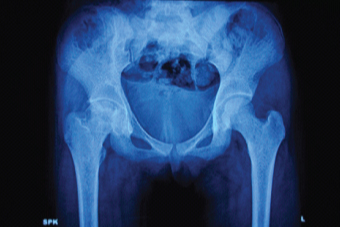

Investigations showed haemoglobin 8.7 g/dl, corrected total count 16,000/mm3, platelets3, 60,000/mm3, Erythrocyte Sedimentation Rate (ESR) 52mm (1h) and C- Reactive Protein (CRP) was 1.2mg/L. Sickling test was negative. Serum ferritin was 1000ng/ml. Frontal X-ray pelvis revealed flattening of the head of right femur with ill-defined sclerotic and lytic areas within. Right hip joint space was reduced [Table/Fig-1]. The radiographic features were suggestive of avascular necrosis of right femoral head (Steinberg class IV) [1]. Magnetic resonance imaging of hip and prothrombotic workup was not performed due to financial constraints.

Frontal radiograph of pelvis.